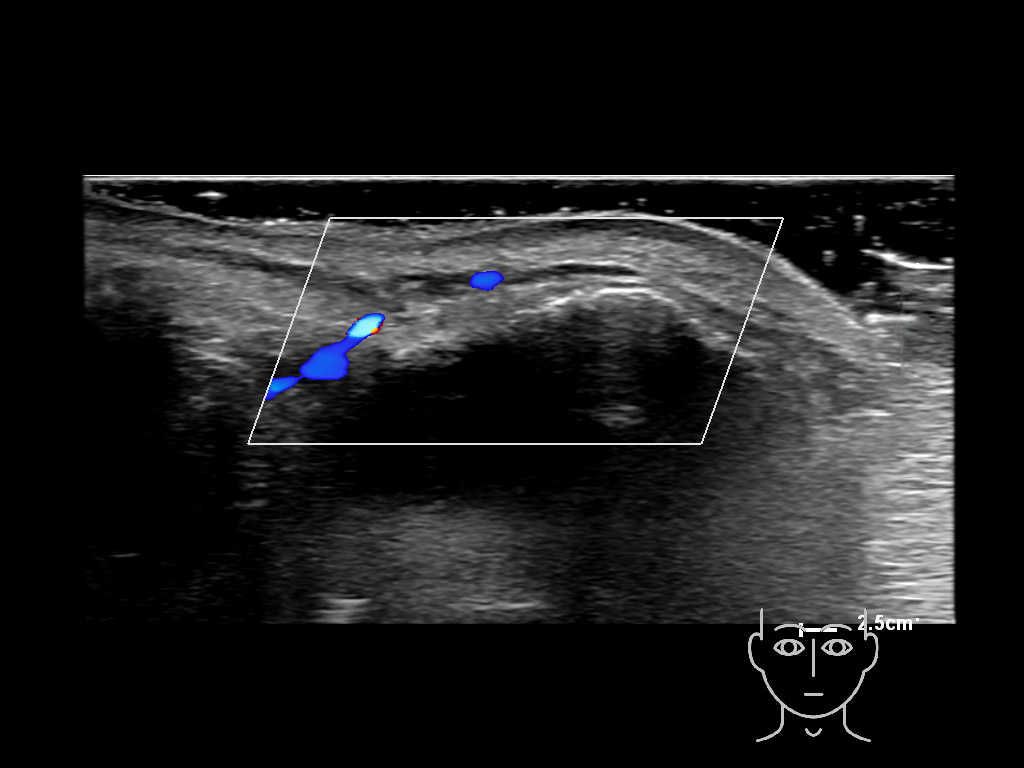

In this section you will learn more about the different layers of the face with the use of ultrasound. When you click on the secondary ultrasound image, you will see the different structures as an overlay. This will help to train yourself to recognize the different layers of the face.

Study the first image to recognize the different layers. If you are sure about the layers, swipe to the second image to view the answer (if applicable).